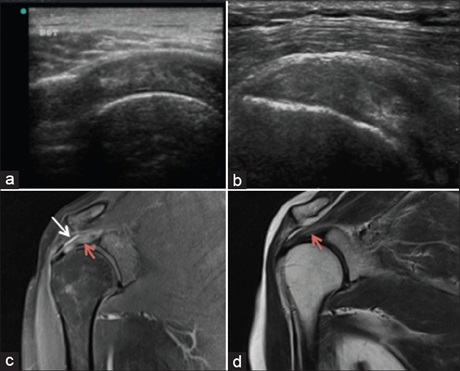

Mural Ameloblastoma of the Mandible: Radiological- Pathological Correlation

Dr. Yadavalli Guruprasad, Dinesh Singh Chauhan, Amit Byatnal, Shrinivas C Koppal, Umashankar Kura, Pradeep Mattighatta Rudraiah (Author)

94-98